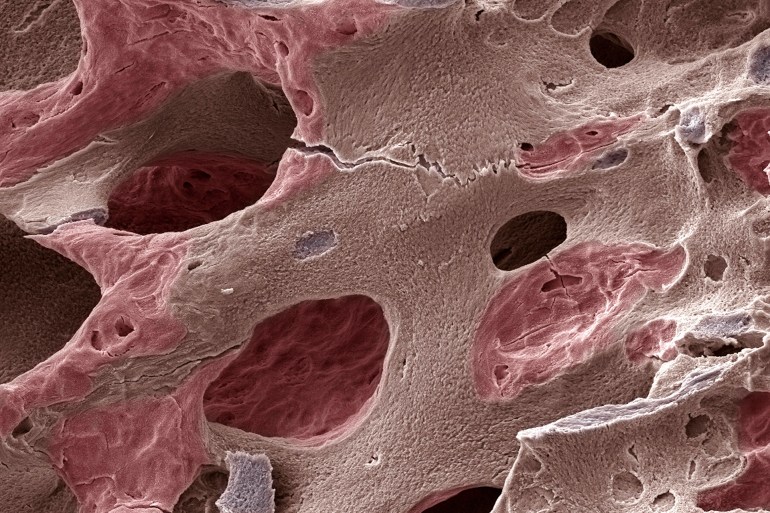

تباطؤ تجديد الخلايا

مع التقدم في السن، يتباطأ معدل تجديد الخلايا العظمية. تصبح الخلايا البانية، المسؤولة عن تكوين العظام الجديدة، أقل نشاطا في حين تظل الخلايا الهادمة المسؤولة عن ارتشاف العظم أكثر نشاطا. ويؤدي هذا الخلل إلى فقدان كتلة العظام وزيادة هشاشتها.